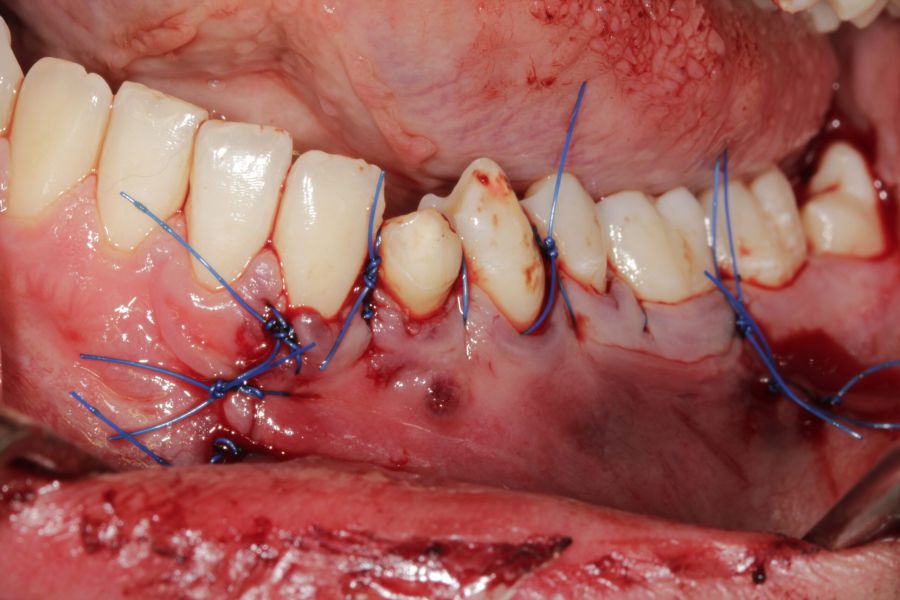

El tratamiento quirúrgico se llevó a cabo bajo sedación combinada con anestesia local de los nervios alveolar inferior, nervio lingual y mentoniano. Se realizó un acceso vestibular con una incisión de Newman (intrasulcular festoneada marginal a espesor total, con una descarga vertical a nivel de la cara mesial del incisivo lateral y distal del primer molar), seguida de un despegamiento mucoperióstico, procediendo a la visualización del foramen mentoniano; posteriormente se llevó a cabo una ostectomía con el fin de visualizar la lesión de la forma más amplia posible, observándose el canino mandibular junto a la cápsula quística por lo que se procedió a la extracción dentaria, bajo control visual del nervio mentoniano, para facilitar la enucleación completa y cuidadosa. Tras la eliminación de la cápsula quística se hizo un legrado cuidadoso de la cavidad residual, evitando el mismo sobre la zona basal con el fin de evitar lesionar el nervio dentario inferior. Una vez finalizada la intervención se procedió a reposicionar el colgajo mucoperióstico, suturando de forma hermética mediante sutura monofilamento de 4-0 (Figuras 5-12).